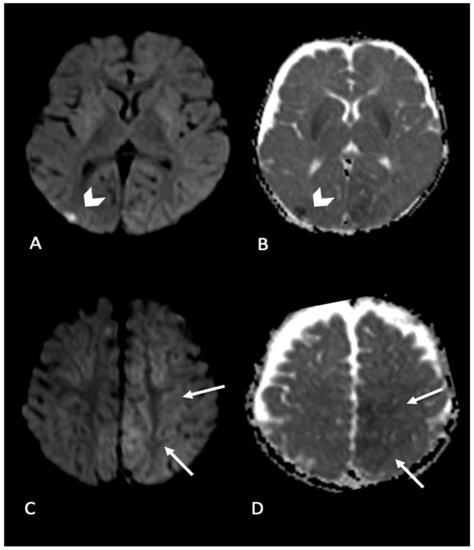

- Chan, Y.-L.; Chu, W.C.W.; Wong, G.W.K.; Yeung, D.K.W. Diffusion-weighted MRI in shaken baby syndrome. Pediatr. Radiol. 2003, 33, 574–577. [Google Scholar] [CrossRef]

- Ichord, R.N.; Naim, M.; Pollock, A.N.; Nance, M.L.; Margulies, S.S.; Christian, C.W. Hypoxic-ischemic injury complicates inflicted and accidental traumatic brain injury in young children: The role of diffusion-weighted imaging. J. Neurotrauma 2007, 24, 106–118. [Google Scholar] [CrossRef]

- Suh, D.Y.; Davis, P.C.; Hopkins, K.L.; Fajman, N.N.; Mapstone, T.B. Nonaccidental pediatric head injury: Diffusion-weighted imaging findings. Neurosurgery 2001, 49, 309–318; discussion 318–320. [Google Scholar] [CrossRef] [PubMed]

- Zimmerman, R.A.; Bilaniuk, L.T.; Farina, L. Non-accidental brain trauma in infants: Diffusion imaging, contributions to understanding the injury process. J. Neuroradiol. 2007, 34, 109–114. [Google Scholar] [CrossRef]

- Orru’, E.; Huisman, T.A.G.M.; Izbudak, I. Prevalence, Patterns, and Clinical Relevance of Hypoxic-Ischemic Injuries in Children Exposed to Abusive Head Trauma. J. Neuroimaging 2018, 28, 608–614. [Google Scholar] [CrossRef]